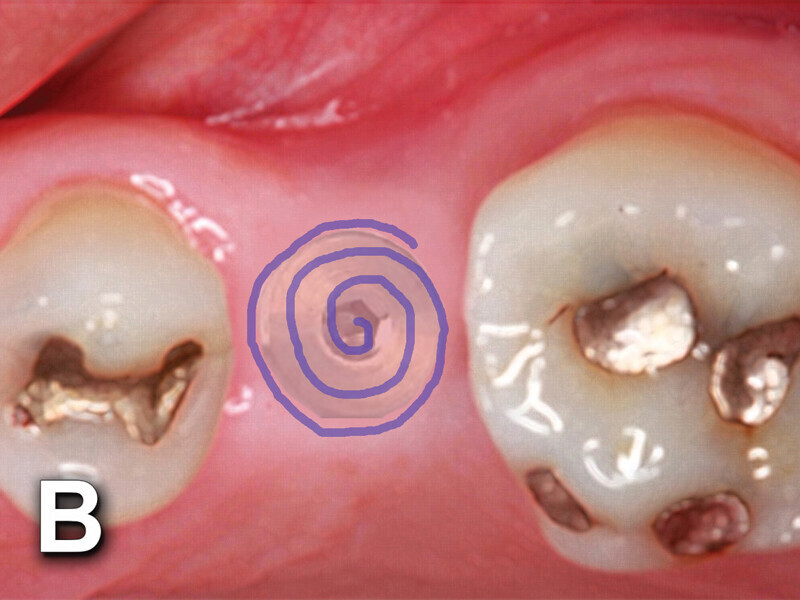

Figs. 4a: Implant to be uncovered (4a) presents with two options depending on width of attached gingiva available. Wide band of attached gingiva will remain after removal of tissue over cover screw, and the diode is utilized in a spiral pattern starting at center until fully exposed (4b). With the narrow band of attached gingiva present, an elliptical cut is made with the diode and tissue is pushed buccally and lingually to preserve the attached gingiva (4c). (Photo provided by Dr. Gregori M. Kurtzman)

Fig. 4b: Implant to be uncovered (4a) presents with two options depending on width of attached gingiva available. Wide band of attached gingiva will remain after removal of tissue over cover screw, and the diode is utilized in a spiral pattern starting at center until fully exposed (4b). With the narrow band of attached gingiva present, an elliptical cut is made with the diode and tissue is pushed buccally and lingually to preserve the attached gingiva (4c). (Photo provided by Dr. Gregori M. Kurtzman)

Fig. 4c: Implant to be uncovered (4a) presents with two options depending on width of attached gingiva available. Wide band of attached gingiva will remain after removal of tissue over cover screw, and the diode is utilized in a spiral pattern starting at center until fully exposed (4b). With the narrow band of attached gingiva present, an elliptical cut is made with the diode and tissue is pushed buccally and lingually to preserve the attached gingiva (4c). (Photo provided by Dr. Gregori M. Kurtzman)